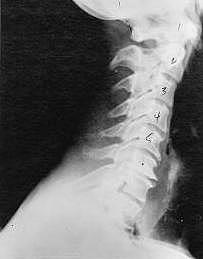

Phase Three - Subluxation Degeneration

Subluxation Degeneration - Phase Three Phase Three Subluxation Degeneration is caused by subluxations that have been continuing on for between 40 and 65 years. This phase has all of the attributes of the previous phases, only worse. The curvatures are abnormal, the disc spaces are vastly decreased and changed. Calcium changes on the spine are abundant in this phase. Normally, people in phase three have a restricted range of motion and probably exhibit symptoms of some kind. In phase three the vertebrae show obvious changes and mutations in shape. Projections made of calcium, sometimes referred to as "spurs or lipping", can be readily seen on x-ray. Chiropractic reconstructive care for patients in phase three ranges from 2.5 years to 3.5 years. This does not mean that at the end of this time that any or all of the calcium changes will be gone. In many instances the body adapts to the presence of the calcium and positive changes can only be measured from a functional standpoint. As before, if Phase Three Subluxation Degeneration is left unchecked it slowly advances onward into the next phase.